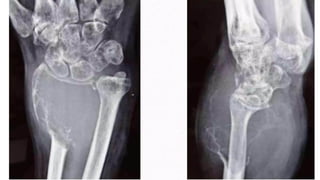

Chondroma/Enchondroma

• • 50% in hands - commonly in phalanges, less commonly in metacarpals

• Cartilaginous tissue is not radiopaque

• • Radiolucent lesion

• Expansion and thinning of overlying cortex

• No periosteal reaction in the absence of fracture

• Z o n e o f t r a n s i t i o n is n a r r o w a n d s c l e r o t i c

• Endosteal scalloping +

• Flecks o f c a l c i fi c a t i o n w i t h i n t h e lesion

• usually purely lytic in phalanges, in other

• locations, enchondromas are expansile, with

• characteristic "rings and arcs" calcifications.

Plain radiograph & CT scan features